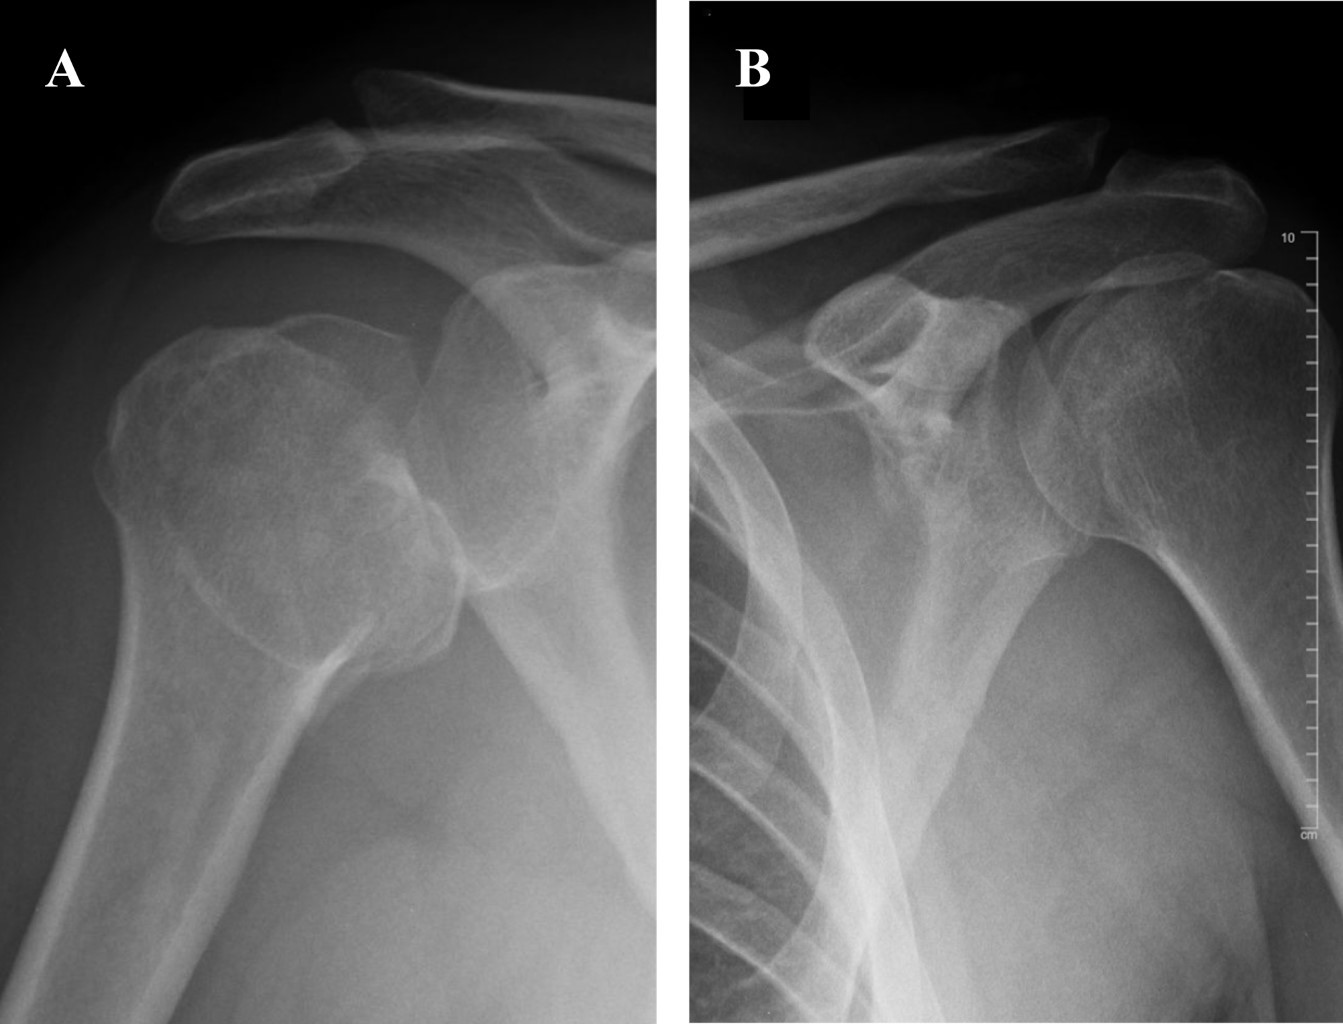

Bilateral Posterior Glenohumeral Fracture dislocation Secondary To A